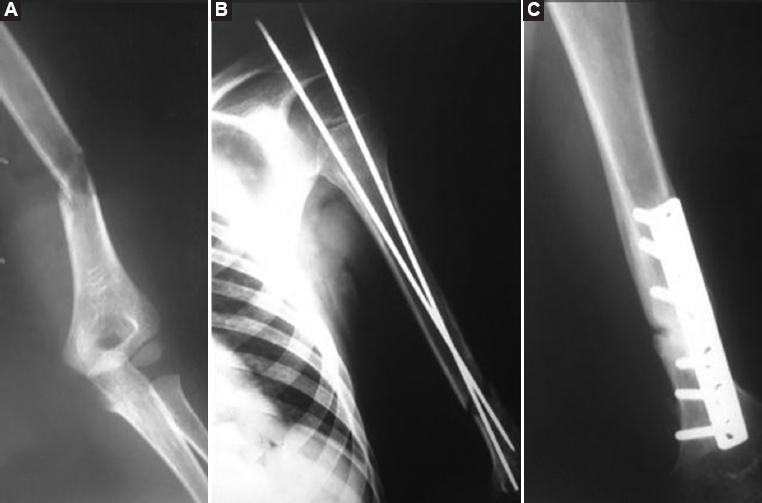

Figure 2 A: Pre-surgical X-ray showing a humerus oblique fracture of the patient. B: Smooth Kirschner wires were used to stabilize the fracture and make soft tissue reparation. C: Control X-ray after nerve and soft tissue repair.

An 8-year-old male patient with severe trauma by getting his left arm jammed in the motor bands of a forage grinder received emergency medical care at the Sanatorio Médico Quirúrgico de los Altos from Tepatitlán de Morelos, Jalisco, México. The patient got an open fracture in the left arm at the junction of the middle third to the distal humerus (Fig. 1) and section of the triceps and biceps muscles leaving the brachialis muscle intact. During surgical exploration, the brachial neurovascular bundle was apparently intact (Fig. 2). The bony fragments were stabilized using 2.0 mm Kirschner wires that were introduced in a retrograde fashion through the humeral medullary cavity and coming out on the shoulder. The open reduction was performed and the nails were pulled back 3 cm to stabilize the fragments. Subsequently, biceps and triceps muscles were repaired. Finally, the subcutaneous tissue and the skin were sutured. During the post-anesthetic recovery period, the patient showed inability to extend the wrist, which was expected after the neurovascular bundle manipulation during reconstruction. Once stable and lucid, a Sarmiento brace was applied to immobilize the limb.

The Kirschner wires were removed during the second surgery to facilitate rehabilitation exercises for biceps and triceps as well as TENS therapy. However, the patient developed horse hoof hypertrophic pseudoarthrosis; thus, the Sarmiento’s brace was removed and the patient underwent surgery to repair the pseudoarthrosis. The medullary space was recanalized and a dynamic compression plate of 3.5 mm with six holes was used for fixation. Union occurred 3 months later.